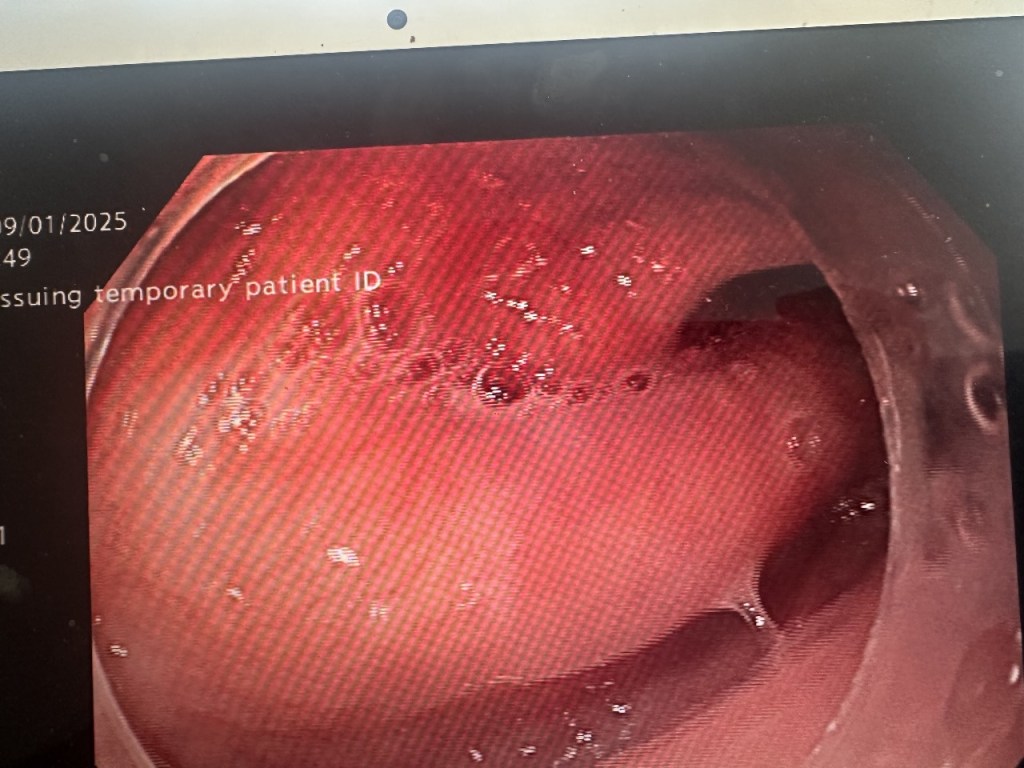

Determined to improve her quality of life, she opted for the Z-POEM (Zenker’s Peroral Endoscopic Myotomy) procedure, an advanced technique that eliminates the obstruction without open surgery. Dr. Gaurav Muktesh, Consultant Gastroenterologist, skillfully performed the procedure, using endoscopic techniques to divide the diverticulum’s septum.

Within 48 hours, the patient was back on her feet and able to eat without difficulty. A follow-up barium swallow confirmed that her esophagus was now functioning normally.